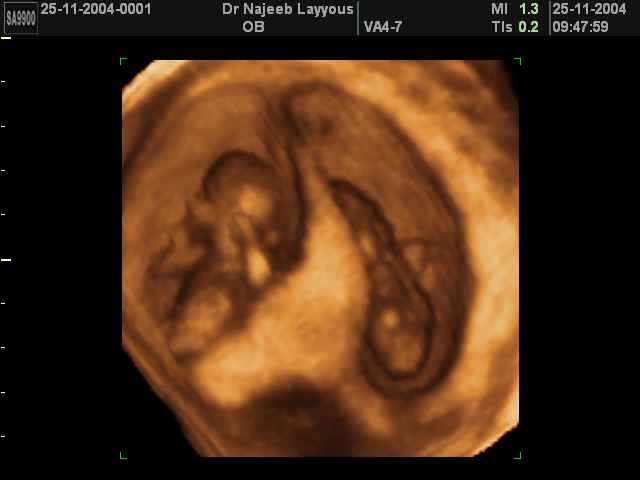

- لقطات فيديو للجنين بجهاز الموجات فوق صوتية رباعي الأبعاد

- صور للجنين في المراحل الأولى من الحمل

- صور لتوائم

صور لتوائم بجهاز الالتراساوند ثلاثي الأبعاد | الدكتور نجيب ليوس